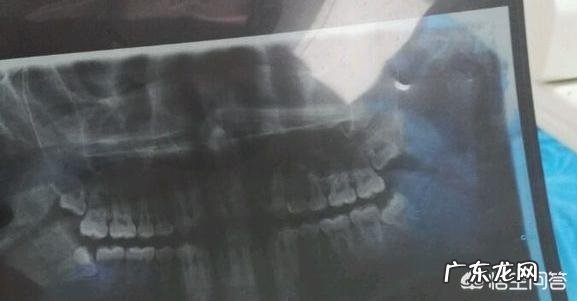

我为什么要拔完牙后想这么多呢?因为实在是太疼了,我是下午四点钟去拔的智齿,一直拔到七点半才结束,整整经历了三个小时,不过这三个小时不是一直在拔,也有医生休息的时间和我休息的时间 。我的这个智齿实在太粗壮了,它有四个根,太坚硬了,为了能让我这个粗壮坚硬的牙根松动些,医生拿上专门的器械对着牙根底端不断的进行上下来回的晃动,以松动这颗智齿,仅这一个操作持续有十来分钟 。拔的时候没有觉得疼,因为打的麻药 。但是在这个时间段,我无数次想不拔了,但是又有一些害羞,而且这个医生还是我认识的熟人,一直坚持到拔完 。

局麻下拔智齿是不疼的,除非牙龈还有炎症,手术到后期才可能有痛感,或者是拔除难度大,比如贴近神经管的,手术时间已经过了一个多钟,麻醉效果没那么好,普通智齿拔除最快不到10分钟,具体看位置长得怎样,要说痛一般在术后比较明显 。

1、其实和拔牙差不多,但智齿长得奇葩,离神经近的,风险较大,如果拔完嘴唇有麻痹情况,那有可能损伤神经了,正常拔牙后痛是正常的,得服用头孢和甲硝唑消肿 。